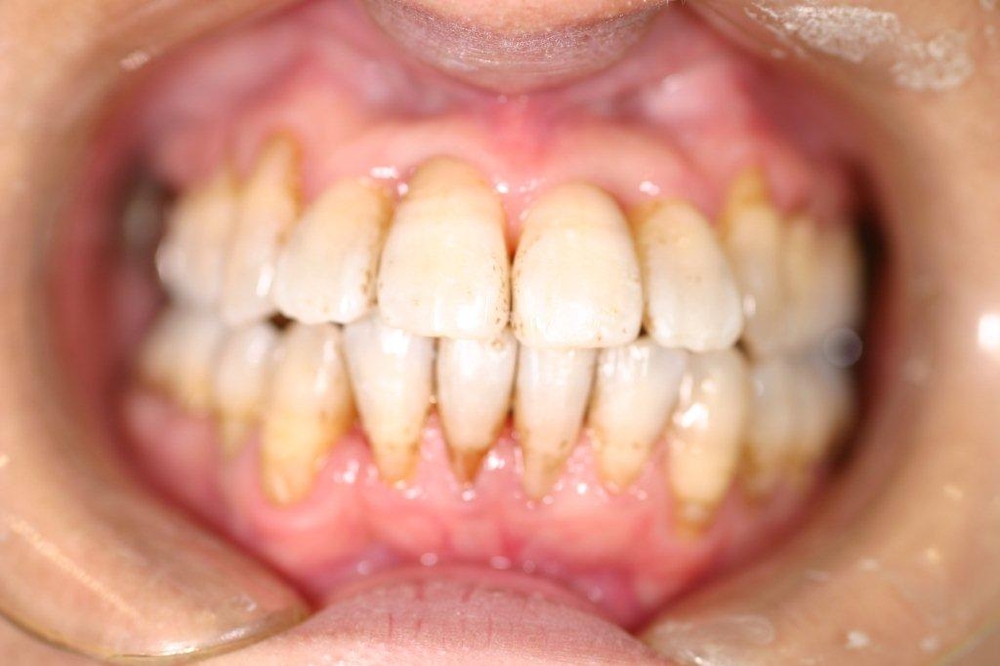

前歯の叢生で歯並びが悪くなっていた患者様の矯正症例

Before

年齢 30代

治療期間 1年6ヶ月

治療費用 900,000円

治療のリスク 特になし